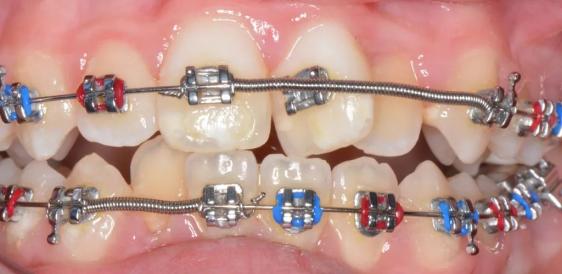

按照这一逻辑,贝格提出了长期以来被奉为圭臬的牙齿正畸标准。贝格提出的方案包括:拔掉前磨牙、将金属丝连接到剩余牙齿上的托槽,在闭合间隙的同时将牙弓拉成一条线来创造更多空间。其他牙齿矫正医生在使用贝格之前先用钢丝将弯曲的牙齿拉直的方法,但他们不会拔出前磨牙,因此拉直的牙齿通常会恢复为弯曲的状态。

最初,许多牙医对通过拉伸健康牙齿以拉直牙弓的想法持反对态度,但贝格的技术行之有效,可以为患者终身提供帮助,并且牙齿也会不断发展以支持它。贝格甚至建议儿童咀嚼含有磨料碳化硅粉的口香糖,以促使其牙齿磨烂,从而完全避免进行正畸治疗。

贝格对于牙齿和颌骨之间不匹配的观点是正确的,但是他弄错了细节。据南伊利诺伊大学的人类学家罗伯·科鲁奇尼(Rob Corruccini)的观点,人类口腔关键的变化不是磨蚀性环境,而是压力环境,这意味着进食期间颌骨会受到机械应力。问题不是牙齿太大,而是下颌太小。